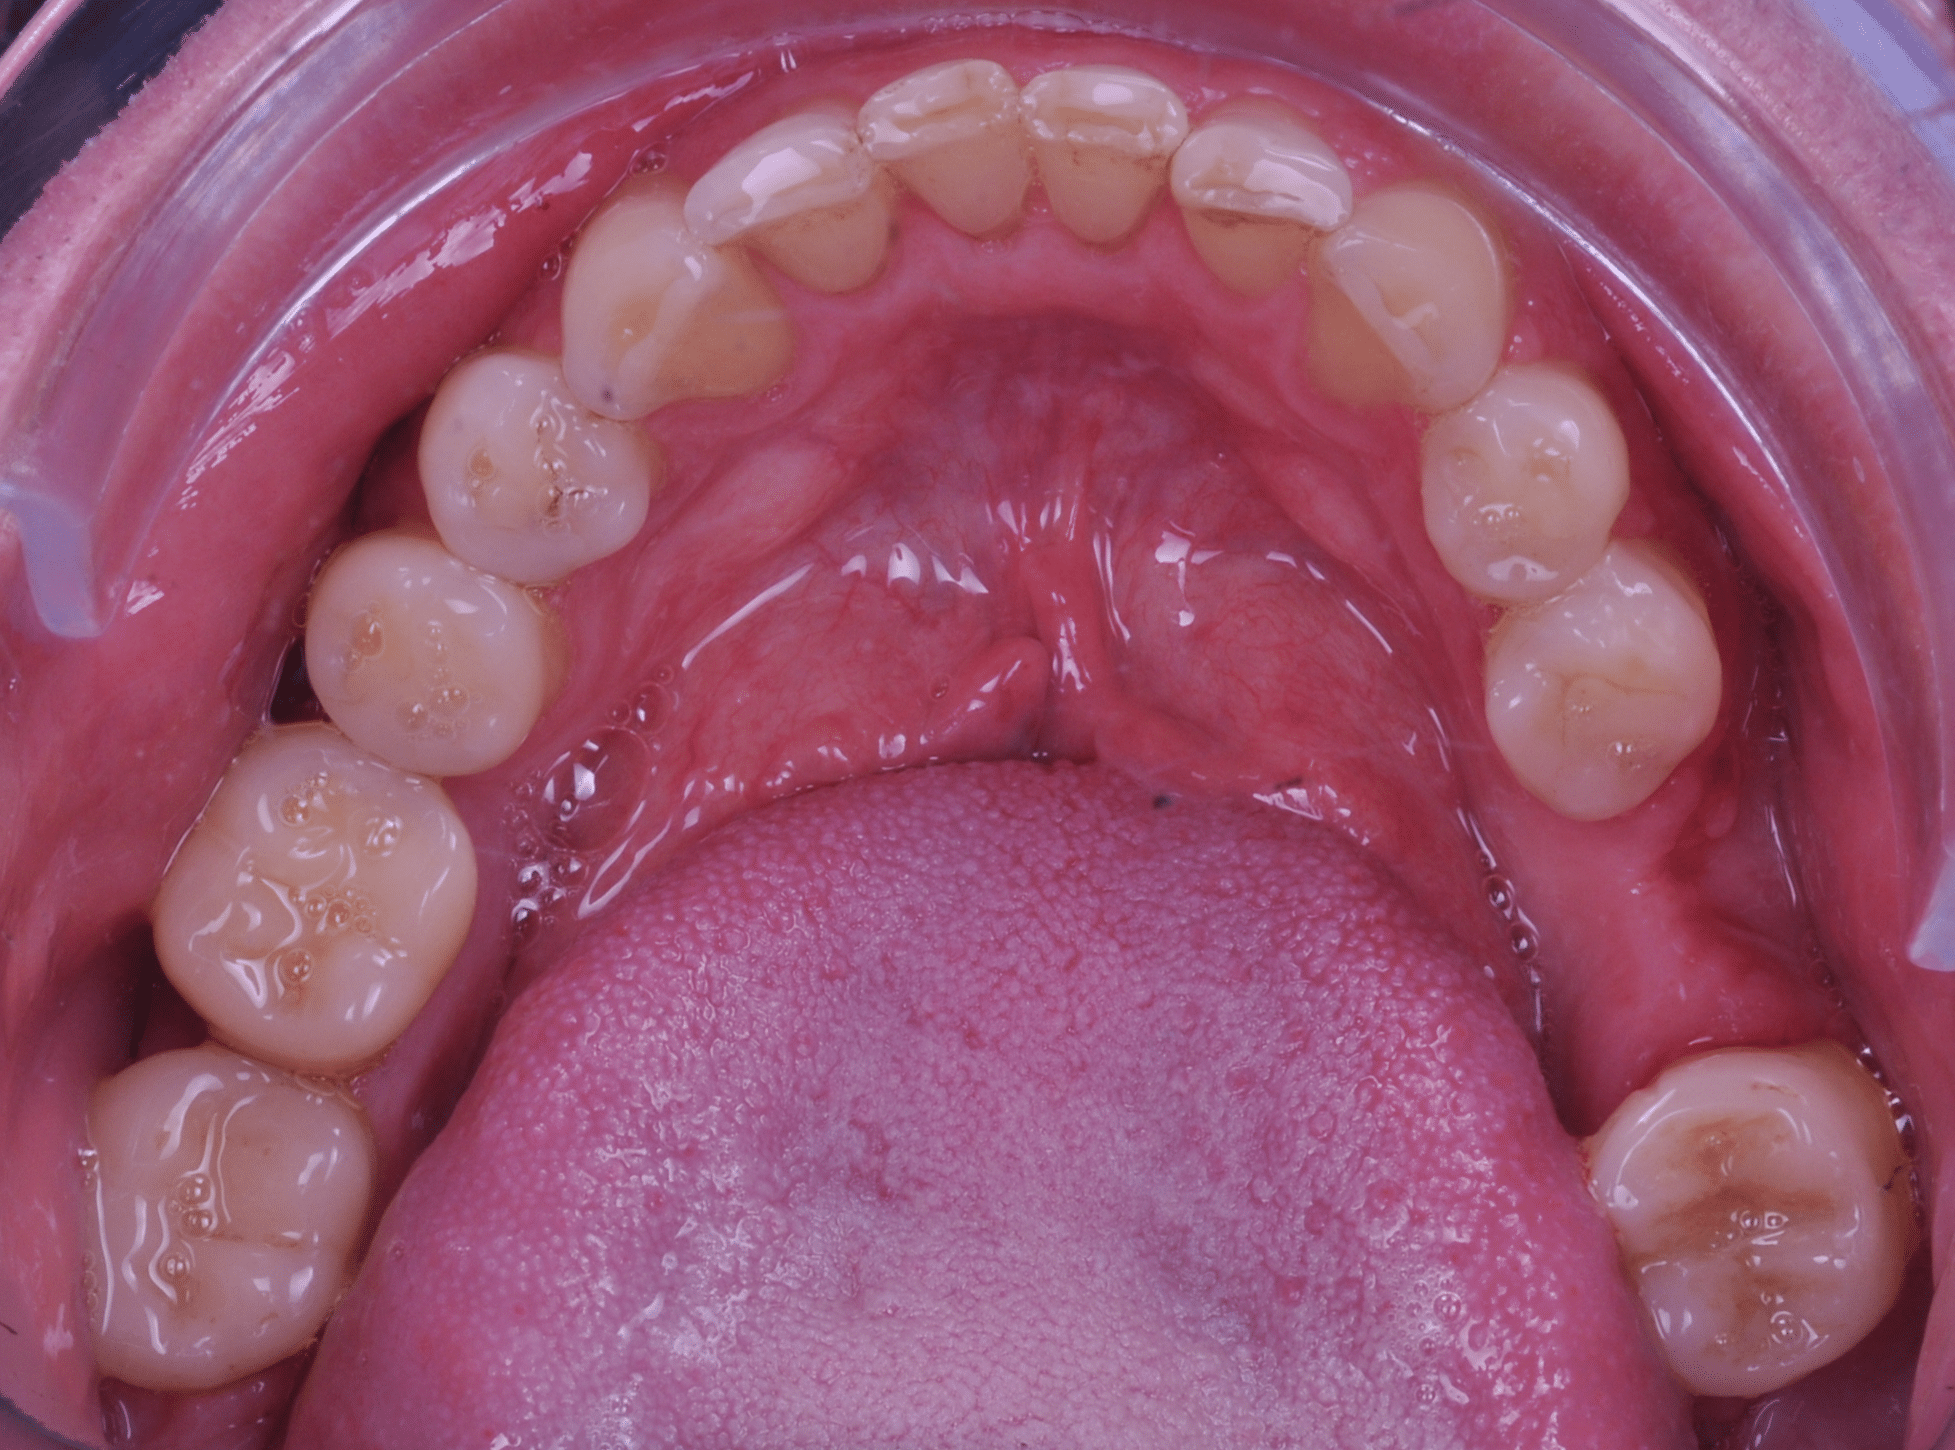

Împreună cu pacientul, am optat pentru inserarea implantelor cu ajutorul ghidului chirurgical pentru a plasa implantul în poziția protetică ideală și pentru a permite realizarea coroanelor insurubate pe implant. A fost efectuată scanarea digitală a arcadelor și a ocluziei pacientului, iar împreună cu tehnicianul radiolog de la DigiRay a fost suprapus fișierul .stl al amprentei digitale peste fișierul .dcm de la CBCT, utilizând software-ul 3Shape.